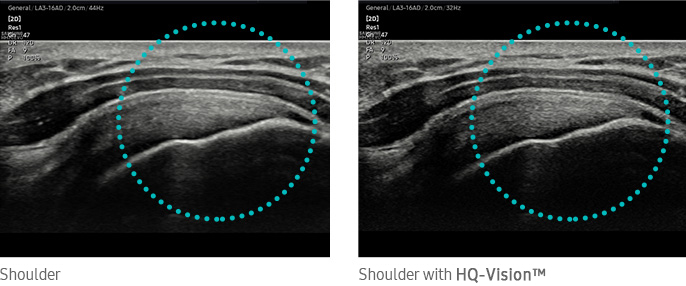

HQ-Vision™¹ provides clear images by mitigating the characteristics of ultrasound images that are slightly blurred than the actual vision.

Shoulder with HQ-VisionTM